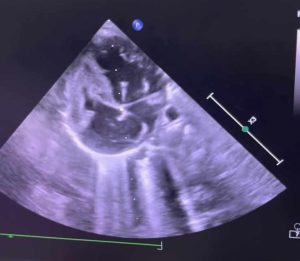

شهدت مستشفى أطفال مصر للتأمين الصحي إنجازًا طبيًا جديدًا يضاف إلى سجلها الحافل في رعاية الأطفال حديثي الولادة، حيث نجح الفريق الطبي بالمستشفى في إجراء أول عملية توسيع للصمام الأورطي بالبالون عن طريق القسطرة لطفلة حديثة الولادة تبلغ من العمر شهرين وتزن 3.600 كجم .

كانت الطفلة تعاني من ضيق شديد بالصمام الأورطي مما تسبب لها في نهجان شديد عند الرضاعة أثر على نموها الطبيعي، حيث تمت العملية الدقيقة بنجاح كبير، وتم نقل الحالة إلى الرعاية المركزة لاستكمال العلاج والمتابعة الطبية، وتتمتع الطفلة الآن بحالة صحية مستقرة وتستعد للخروج والمتابعة الدورية في العيادات الخارجية.